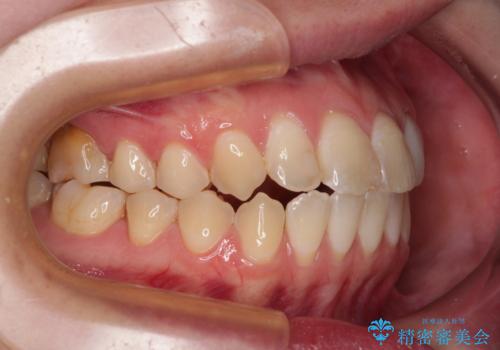

開咬を治す インビザラインによる矯正治療

- 上下前歯の開咬を気にして来院された患者様です。

開咬はインビザラインを用いると有意に改善ができるため、インビザラインによる矯正治療を行うこととしました。

途中1年8ヶ月ほど来院されず、久しぶりの来院後は治療が面倒とのことで、前歯の叢生や隙間に不十分な点が残った状態での終了となりました。